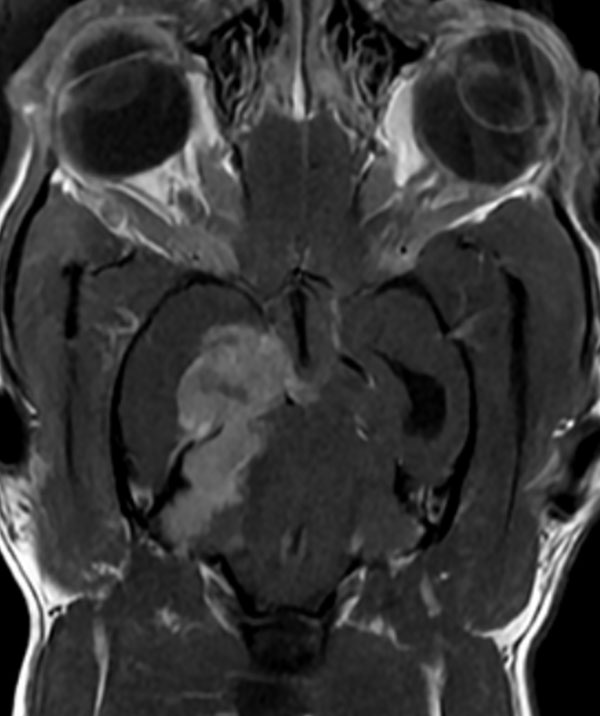

신경외과(Neurosurgery)는 신경계의 질환이나 부상을 외과적 방법으로 치료하는 분야입니다. 신경계는 뇌, 척수, 말초 신경으로 구성되어 있으며, 신경외과는 이러한 신경계의 질환, 손상, 기형 등에 대한 수술적 치료를 담당합니다. 고양이를 포함한 동물들의 신경계 질환은 때로는 생명에 위협을 가할 수 있으며, 빠른 치료가 필요합니다.